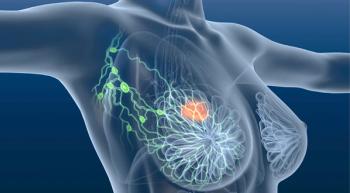

The phase 1/2 study will assess next-generation immunotherapy alone and in combination with an immune checkpoint inhibitor in metastatic breast cancer.

A phase 2 study for patients with HR-positive, HER2-negative metastatic breast cancer will be evaluating alisertib plus endocrine therapy.

The phase 2 INVINCIBLE-4 clinical trial is currently underway in patients with localized triple-negative breast cancer.

A new arm of a clinical trial will investigate (Z)-endoxifen plus Verzenio in patients with ER-positive, HER2-negative breast cancer.

Research is underway on the immune-stimulating antibody conjugate BDC-1001’s effectiveness against HER2-positive cancers when combined with Perjeta, according to data presented at SABCS.